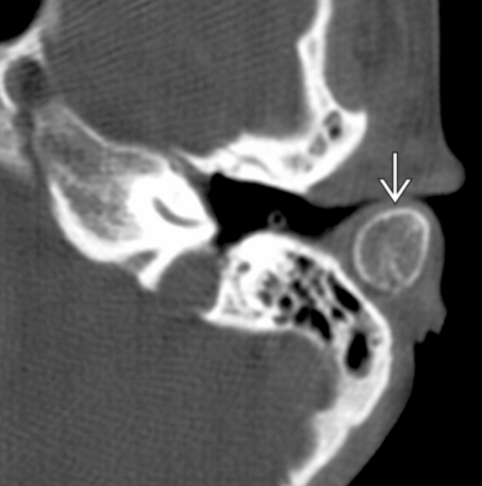

Axial bone CT shows an ovoid bone with cortex and marrow space in the location of the posterior portion of the cartilaginous EAC. No stalk of attachment is visible. Accessory ossicles are rare in this area.